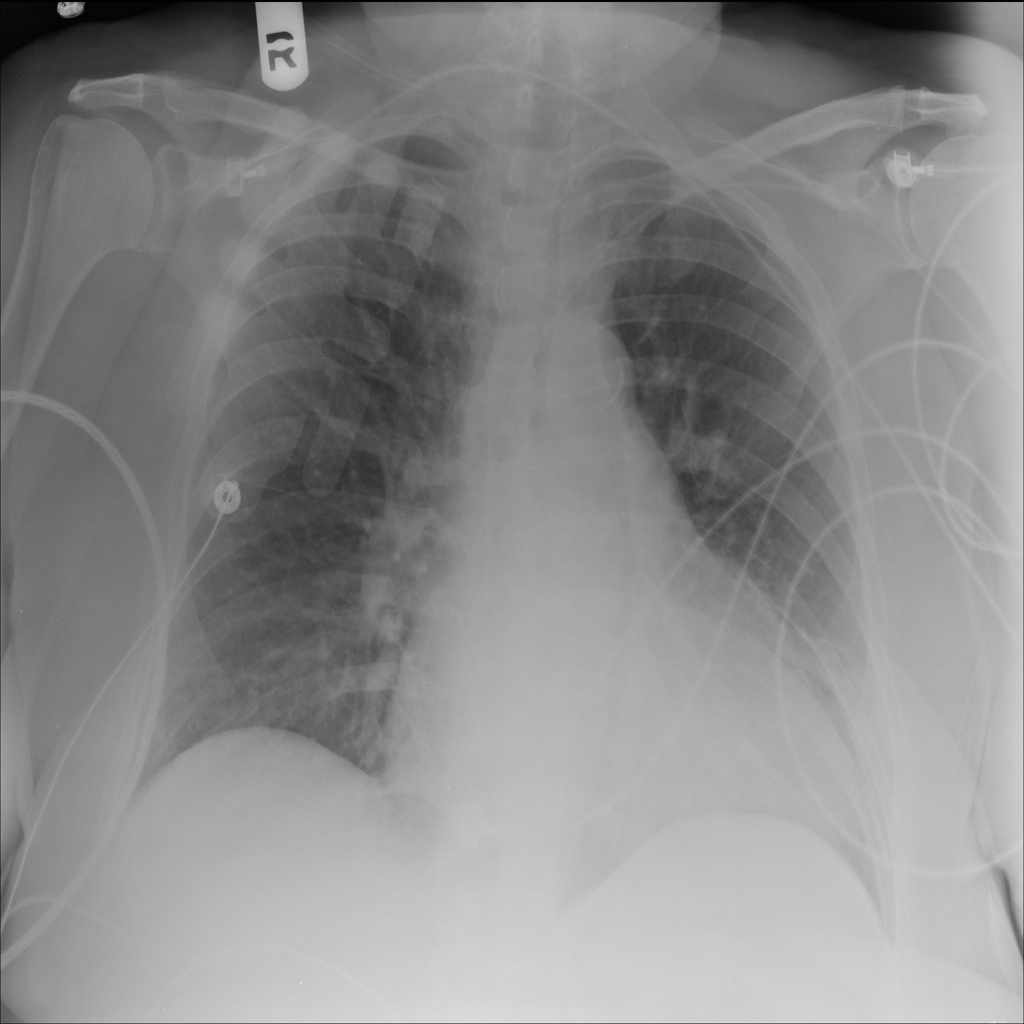

PAT-5092 · IMG-004Cardiomegaly

PAT-5092 · IMG-004

AP